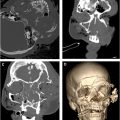

The gold standard for identification and evaluation of mandible fractures is a maxillofacial computed tomography (CT) with cuts at 1 mm or less. Three-dimensional reconstruction of CT scans facilitates understanding of geometric relationships and fracture fragment orientation. However, minimally displaced or hairline fractures may be missed due to volume averaging. The axial, coronal, and sagittal cuts should be carefully evaluated for every patient. Panoramic tomography (eg, panorex) may be used for evaluation of mandible fractures and involves lower cost and radiation exposure. Some surgeons may routinely use this modality of imaging, particularly for postoperative assessment of plating ( Fig. 5 ). However, the lack of 3-dimensional relationships makes appreciation of fracture angulation difficult. CT has higher sensitivity in fracture identification and decreased interpretation error.